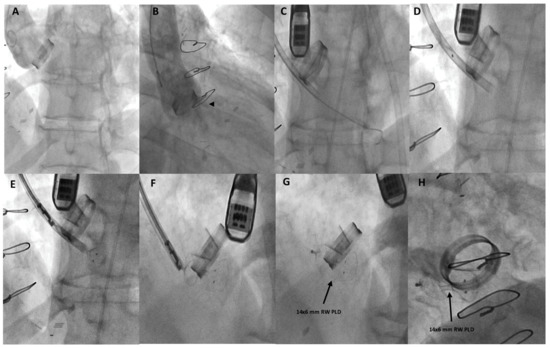

Paravalvular Leakages after Surgical Aortic-Valve Replacement and after Transcatheter Aortic-Valve Implantation: Strategies to Increase the Success Rate of Percutaneous Closure

Moderate to severe paravalvular-leak (PVL) regurgitation after surgical aortic-valve replacement or after transcatheter valve implantation represents a well-known complication associated with symptoms related to heart failure, hemolysis, or both in patients with multiple comorbidities and with poor prognostic outcomes. The transcatheter closure of [...] Read more.

Moderate to severe paravalvular-leak (PVL) regurgitation after surgical aortic-valve replacement or after transcatheter valve implantation represents a well-known complication associated with symptoms related to heart failure, hemolysis, or both in patients with multiple comorbidities and with poor prognostic outcomes. The transcatheter closure of aortic paravalvular leaks (APVLs) is currently considered a valid alternative to cardiac surgery. Nevertheless, careful patient selection, optimal cardiac imaging for intraprocedural guidance, and expert operators are key for success. Although technically demanding, particularly in APVLs after transcatheter valve implantation, catheter-based closure is an effective, less invasive, and often the only option for high-risk patients with symptomatic PVL regurgitation. Full article